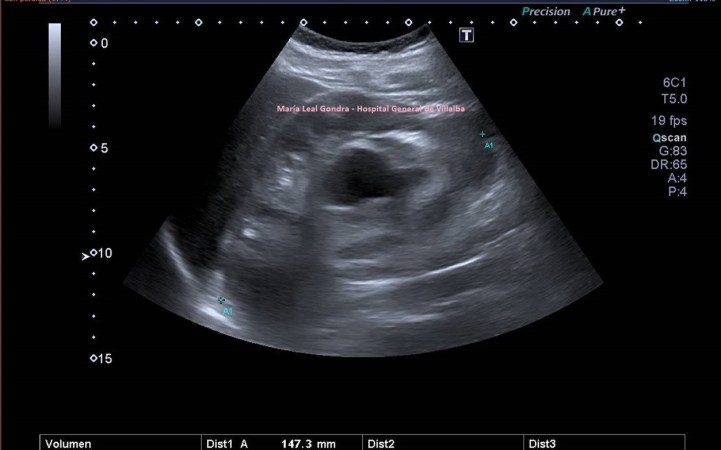

En la imagen 2 ves una lesión grande, redonda, de aspecto quístico, anecoica de bordes bien definidos y finos, con buena transmisión de sonido.

2

En la imagen 3,4 y 5 ves una lesión en la misma localización, ecogénica, sólida, heterogénea, redonda y de gran tamaño, lobulada. Tiene vascularización y es heterogénea. Flecha amarilla.

Ambas lesiones ubicadas en el polo superior del riñón derecho. más profundo que el polo inferior, normal, desde el punto de vista ecográfico, según la disposición de la sonda y la situación espacial del riñón en la anatomía humana de modo general, siempre a expensas de rotaciones y variantes de la normalidad.

Nos quedamos con la imagen 3 y 4, y en este caso observamos que es una lesión que la paciente ya tenía años atrás y que fue objetivada ecográficamente, de menor tamaño y que en tres años ha crecido considerablemente y que no ha sido tratada durante este tiempo por motivos que desconozco.